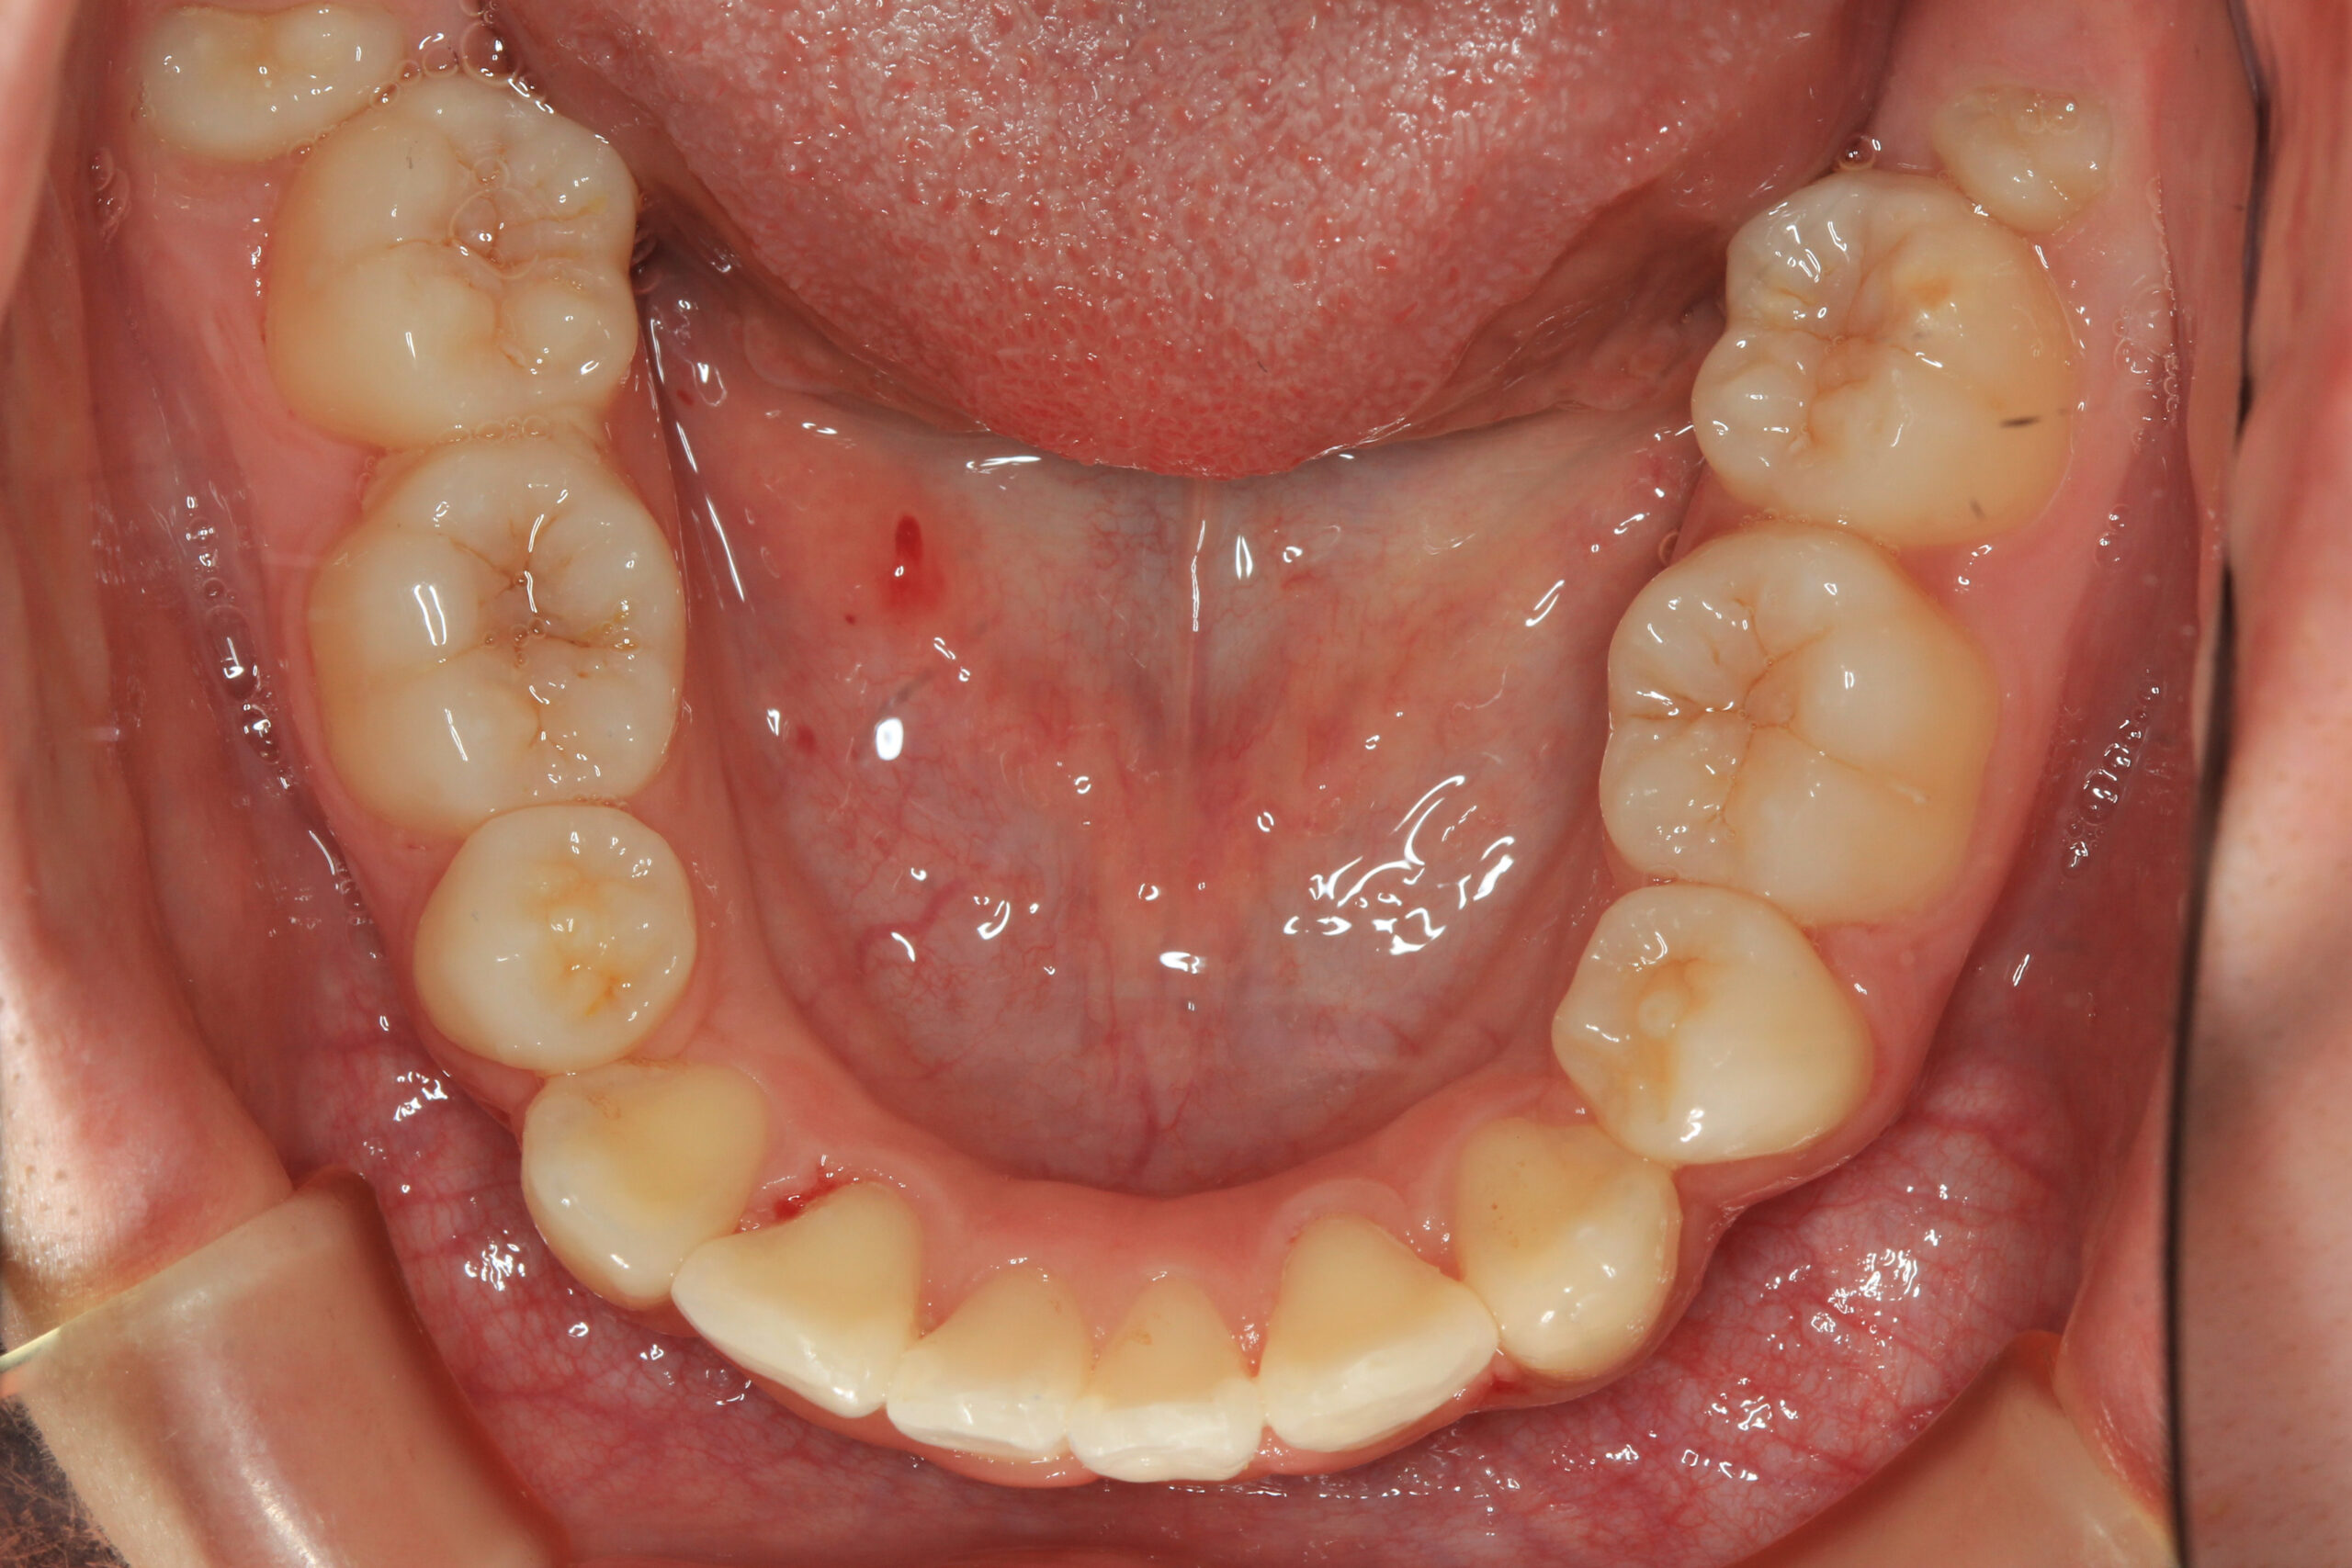

下顎も左右の小臼歯を抜歯後改善しました。

上の写真と比べてください、オーバージェット感も抜群に綺麗になりました。

通常抜歯矯正となりますと大体3年前後かかると言うのが普通なのですが今回は文明の利器である加速矯正装置をインビザラインと併用し僅か1年3か月でこの様に改善出来ました。

ここまでのガタガタをインビザラインで抜歯矯正できればもうワイヤー矯正なんて必要ないんじゃないかと思うくらい綺麗な出来です。